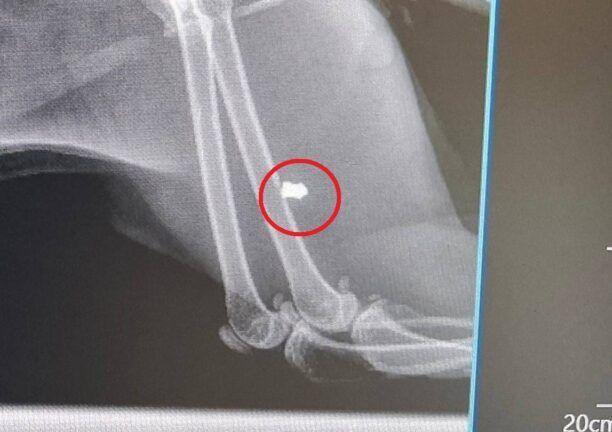

H γάτα μεταφέρθηκε ζωντανή σε κατάσταση σοκ στο Κτηνιατρικό Κέντρο Σύρου «SYMVIOSIS». Το σφαιρίδιο του αεροβόλου βρέθηκε μεν στο πόδι αλλά είχε κάνει διαδρομή από το σύστοιχο κενεώνα, που ήταν το σημείο εισόδου. Το ζώο κατέληξε στο κτηνιατρείο.